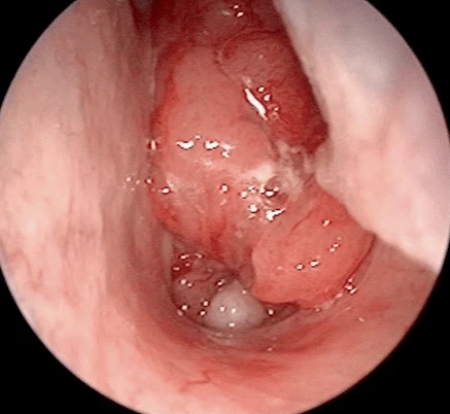

Viêm họng mạn tính tái phát nhiều lần sẽ gây nên hiện tượng áp xe, viêm, tấy xung quanh họng, lưỡi gà, viêm amidan,…

Lúc này, bệnh lan từ vùng họng tới các cơ quan hô hấp xung quanh, gây ra các bệnh lý viêm nhiễm như: viêm xoang, viêm mũi, viêm phế quản, khí quản, thanh quản, viêm phổi,…